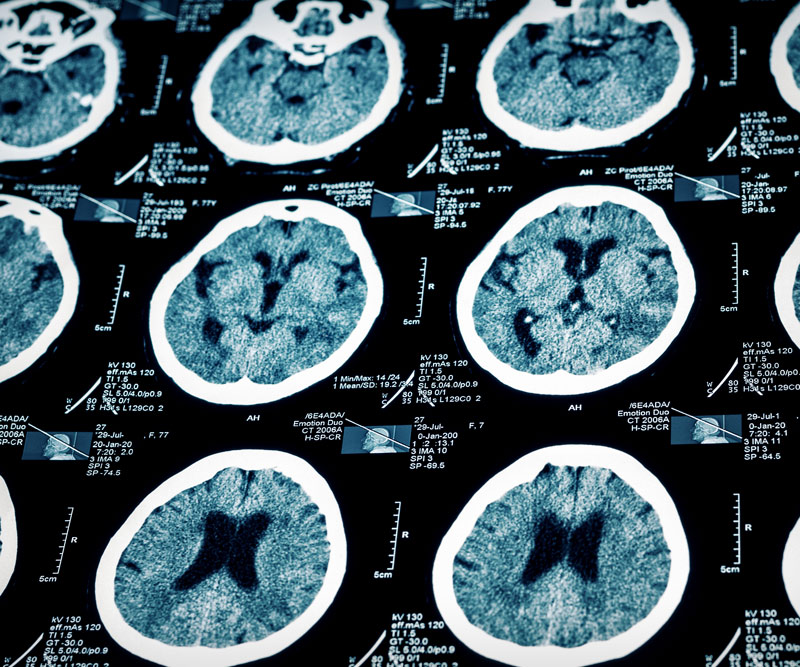

Current thinking is that the area of the brain where we appreciate and remember music may be less susceptible to the degeneration that is caused by Alzheimer’s disease. Also interesting is that certain tastes and smells may trigger memories of past events – even in people with dementia.